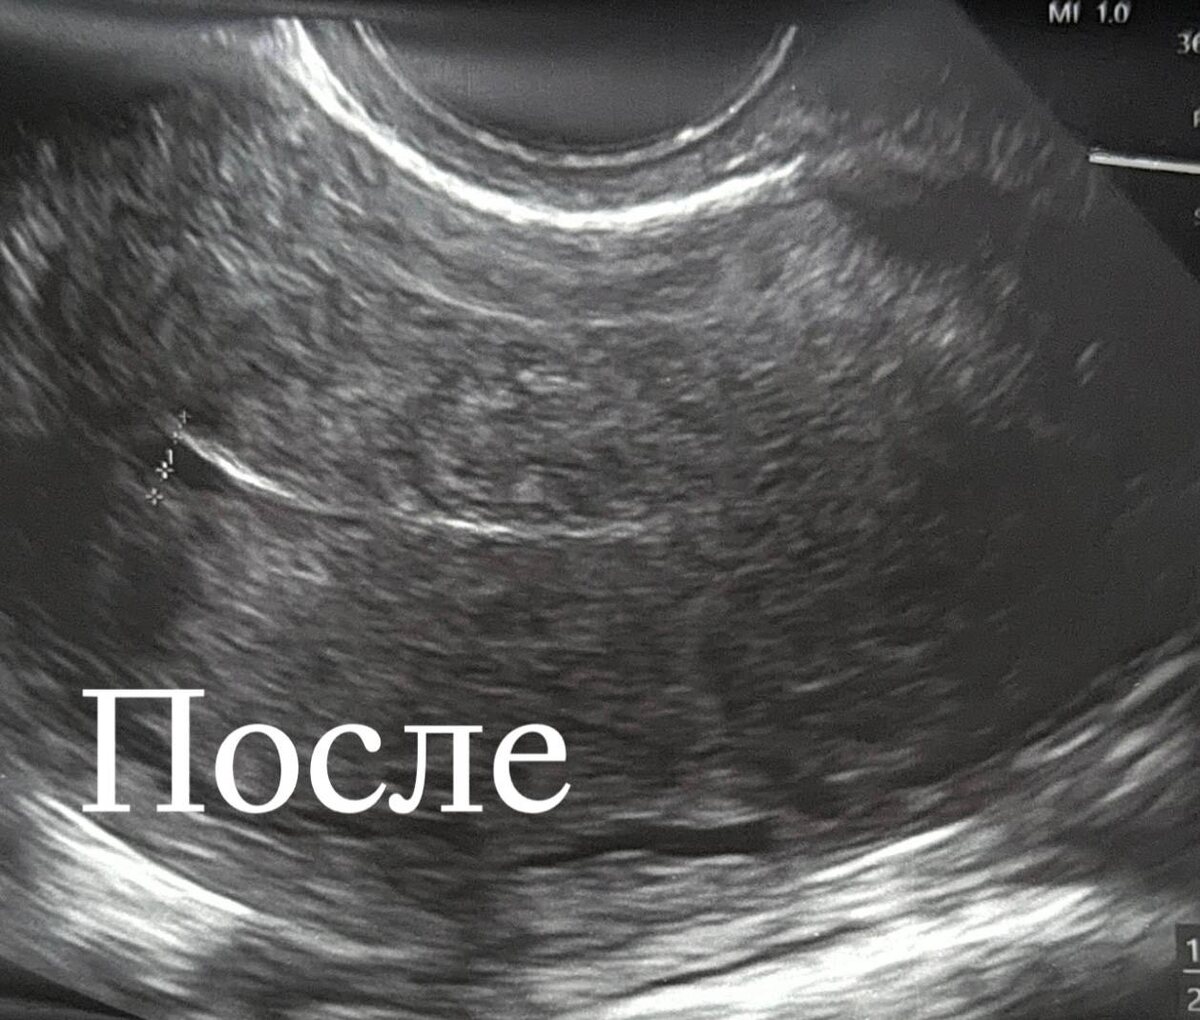

Случай 2025 года: пациентка, планирующая первую беременность, и сложный узел с нарушением питания. Из-за размытых границ опухоли мы не стали рисковать и провели лечение в два этапа с интервалом в 3 месяца. Методом гистерорезектоскопии, шаг за шагом, мы освободили полость матки.

Итог: Матка сохранена, полость идеальна, репродуктивный шанс защищен.